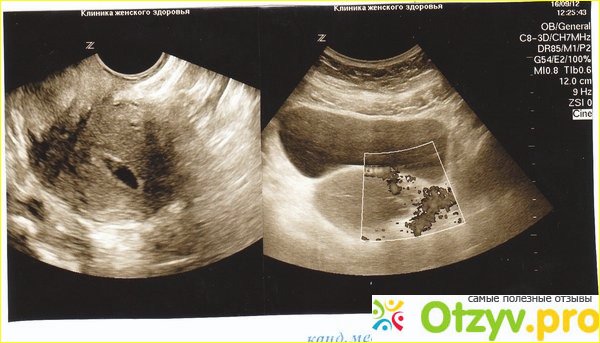

Метросальпингография или МСГ - это метод исследования и рентгено-диагностики полости матки и маточных труб. При применении метросальпиногографии используется контрастное вещество, которое вводится в исследуемый орган, тем самым увеличивая чёткость рентгеновского снимка. Этим методом пользуются при выявлении причин бесплодия, самопроизвольных обортах, при эндометриозе, аномалиях органов, маточном кровотечении, миоме матки и при некоторых гинекологических заболеваниях.

Противопоказано проводить диагностику таким образом во время беременности, при воспалении органов малого таза, при повышенной чувствительности к контрастному веществу и при простудных заболеваниях. Пере тем, как провести подобную диагностику следует провести несколько подготовительных процедур. Обязательно сдать анализы, опустошить мочевой пузырь и наполнить желудок. Процедура МСГ проводится через две недели после окончания менструации в клинических условиях. При условии отсутствия противопоказаний. Для исключения болезненных ощущений при МСГ делается обезболивание. Операция проводится в рентгенологическом кабинете на гинекологическом кресле. После того, как оперируемая поверхность обрабатывается йодом, в шейку матки вводится жирорастворимое и водорастворимое контрастные вещества, не больше 15 мг.Отзыв о Мсг Это йодлипол, верографин и другие. По мере того, как происходит заполнение матки и маточных труб контрастным препаратом, проводится рентгеноскопия. И первый снимок можно делать уже через пять минут, спустя ещё несколько минут - второй. По снимкам определяют состояние исследуемых органов, проверяют на наличие спаек и проходимость. Этот способ МГС является достаточно болезненным, из-за использования специальных медицинских щипцов для обеспечения давления в матке. Но есть и другой - это селективная метросальпингография, при котором не требуются зажимы. Все наблюдения специалист может проводить по монитору.Мсг фото1 В момент проведения рентгеновского снимка, врачу не обязательно покидать кабинет, и у него есть возможность самостоятельно регулировать ввод контрастного вещества. При таком способе диагностика обеспечивает получение наибольшего количества информации. При обнаружении непроходимости в маточных трубах, устанавливает специальный катетер, который проходимость восстанавливает. На все эти манипуляции уходит примерно 20 минут.